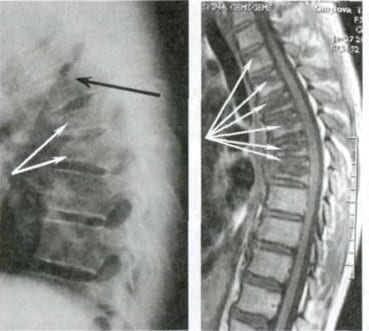

Bu rentgen suratiga qarang. Bu — 44 yoshli insonning umurtqasi, lekin u qarigan odamnikidek ko‘rinadi. Avvallari bu turdagi shikastlanishlar odatda 60 yoshdan keyin paydo bo‘lardi, ammo hozir u 40 yosh atrofidagi odamlarda juda keng tarqalgan. Bunday o‘zgarishlar yosh o‘tgan sayin kuchayadi va ularni e’tiborsiz qoldirish to‘liq harakatsizlikka olib kelishi mumkin.

44 yoshli bemorning umurtqasi: hammasi oddiy og‘riqdan boshlandi, ammo bir hafta ichida churra paydo bo‘ldi, ikki hafta ichida esa umurtqalar siljishi, asab siqilishi va nogironlik aravachasiga ehtiyoj yuzaga keldi.